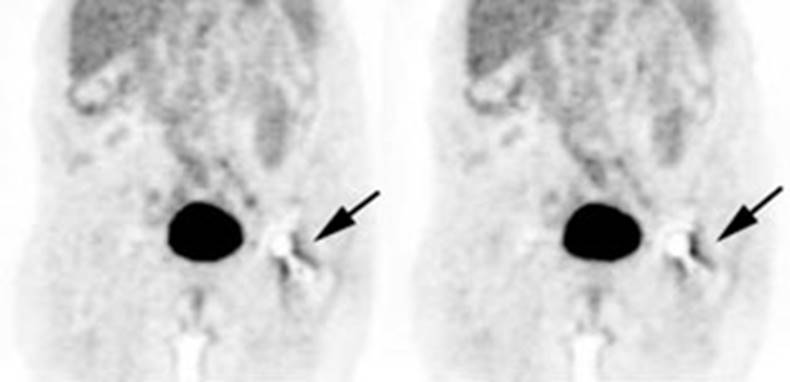

Figure 6 - Genitourinary activity: The image below

demonstrates activity within the collecting system of a transplanted kidney

(black arrows). This should not be mistaken for an abnormality.